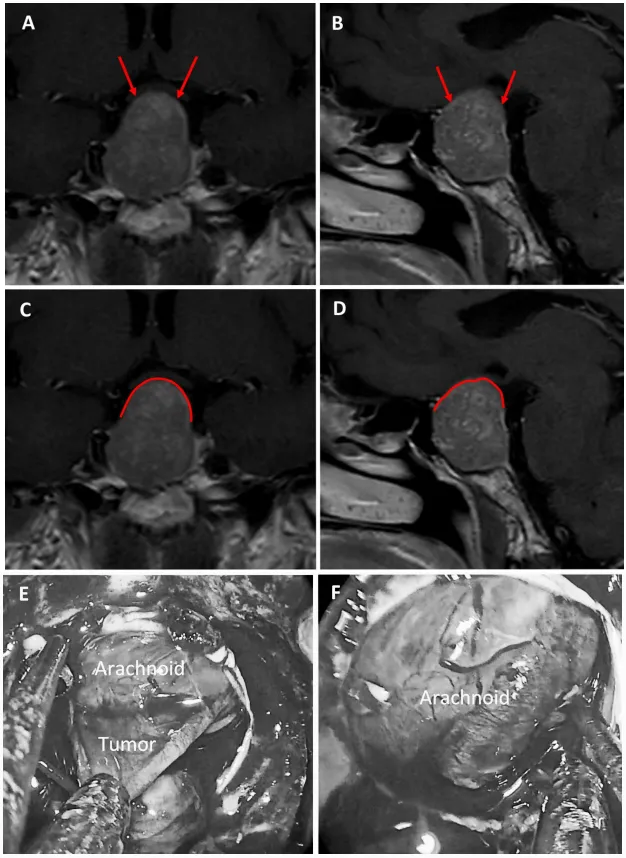

图5展示56岁女性ACTH腺瘤患者。a和b为术前MRI图像,黄色箭头指示厚度大于1毫米的强化屏障区,红色箭头指示厚度小于1毫米的薄弱屏障区;c和d为术前MRI,黄色标记线标示强韧屏障区域,红色标记线标示薄弱屏障区域;e为术中图像,显示由垂体腺与蛛网膜共同构成的混合屏障结构。